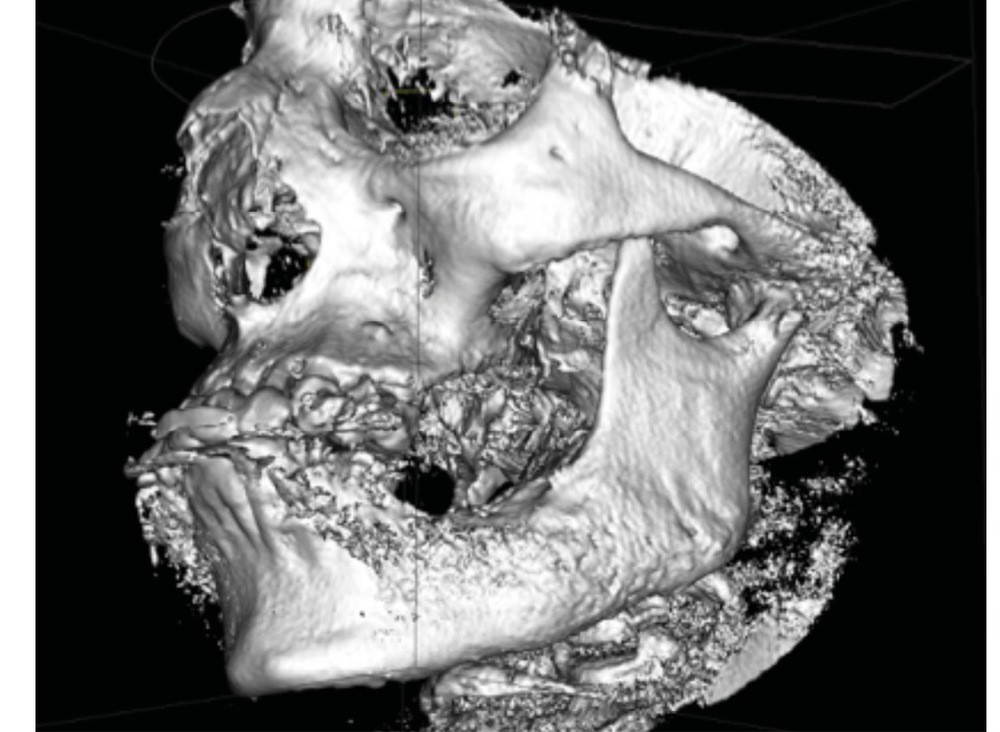

La mandibule est le site de prédilection au niveau cranio-facial.

Un trismus peut accompagner les douleurs, ainsi qu’une tuméfaction génienne basse intéressant la branche horizontale et l’angle mandibulaire, avec voussure vestibulaire. L’absence de fistule gingivale, d’adénopathies cervicales et de paresthésies labio-mentonnières fait évoquer ce diagnostic. Parfois, une biopsie peut être pratiquée.

L’examen radiologique (scanner ou tomographie a faisceau conique) est très évocateur. Il montre un épaississement périosté avec « aspect mixte » de l’os médullaire et des « perforations corticales ».